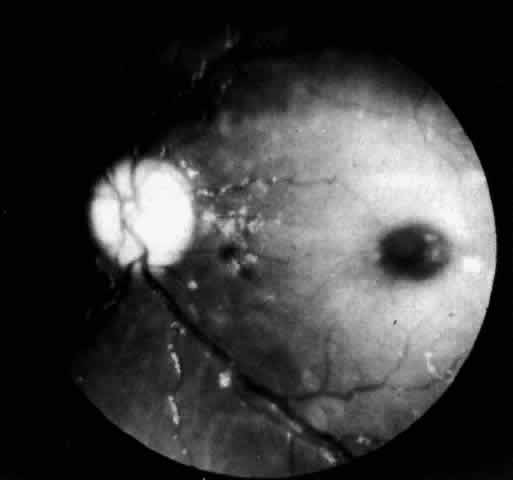

In three patients with type III subacute juvenile neuronopathic Gaucher's disease however, the retina showed a unique retinopathy. The findings in Cogan's case 1 are described: “Both fundi showed discrete white spots randomly distributed in the posterior fundus, especially along the inferior vascular arcades (Fig. 8). The spots varied in diameter from just visible to approximately 0.1 mm and were situated in the superficial retina or on the surface of the retina. Several covered the retinal vessels. The disc and retinal vessels were normal.” The child, an 11-year-old boy, had normal acuity and a full field of vision by confrontation. He had presented at age 3 years with splenomegaly.

Fig. 8. Fundus of a patient with type III subacute juvenile neuronopathic Gaucher"s disease showing discrete white spots in or on the retina along the inferior vascular arcades. At least one spot overlies a vein. The optic disc and retinal vessels were normal. (Cogan DG, Chu FC, Gittinger J, Tyshsen L: Fundal abnormalities of Gaucher"s disease. Arch Ophthalmol 98:2202, 1980. Copyright © 1980, American Medical Association)

Normal vision and similar retinal abnormalities were observed in a mildly mentally retarded 18-year-old woman (case 2) presenting with splenomegaly at age 1 year and in a 6½-year-old boy (case 3) noted to have hepatosplenomegaly in the first year of life. The patients in cases 1 and 3 had conspicuous supranuclear defects of eye movement.